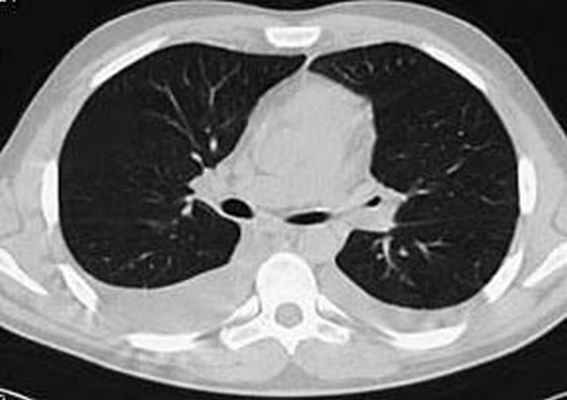

В течение недели прошла одышка, уменьшилась тахикардия, над легкими перестали выслушиваться хрипы, подверглись обратному развитию проявления геморрагического васкулита и ливедо. Однократно проведена плевральная пункция с удалением 700 мл выпота соломенно-желтого цвета. При контрольной КТ органов грудной клетки через неделю лечения лимфаденопатия средостения и изменения легочной ткани по типу “мaтового стекла” не определялись (рис. 6). В стационаре прибавил в весе 5 кг. Клинический анализ крови нормализовался с марта 2007 г.

| Рис. 6. КТ через месяц лечения: отсутствуют изменения в средостении и легочной ткани | |